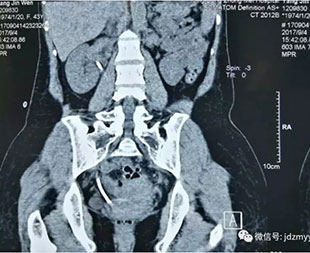

泌尿外科主要治疗范围有:各种尿结石和复杂性肾结石;肾脏和膀胱肿瘤;前列腺增生和前列腺炎;睾丸附睾的炎症和肿瘤;睾丸精索鞘膜积液;各种泌尿系损伤;泌尿系先天性畸形如尿道下裂、隐睾、肾盂输尿管连接部狭窄所导致的肾积水等等。